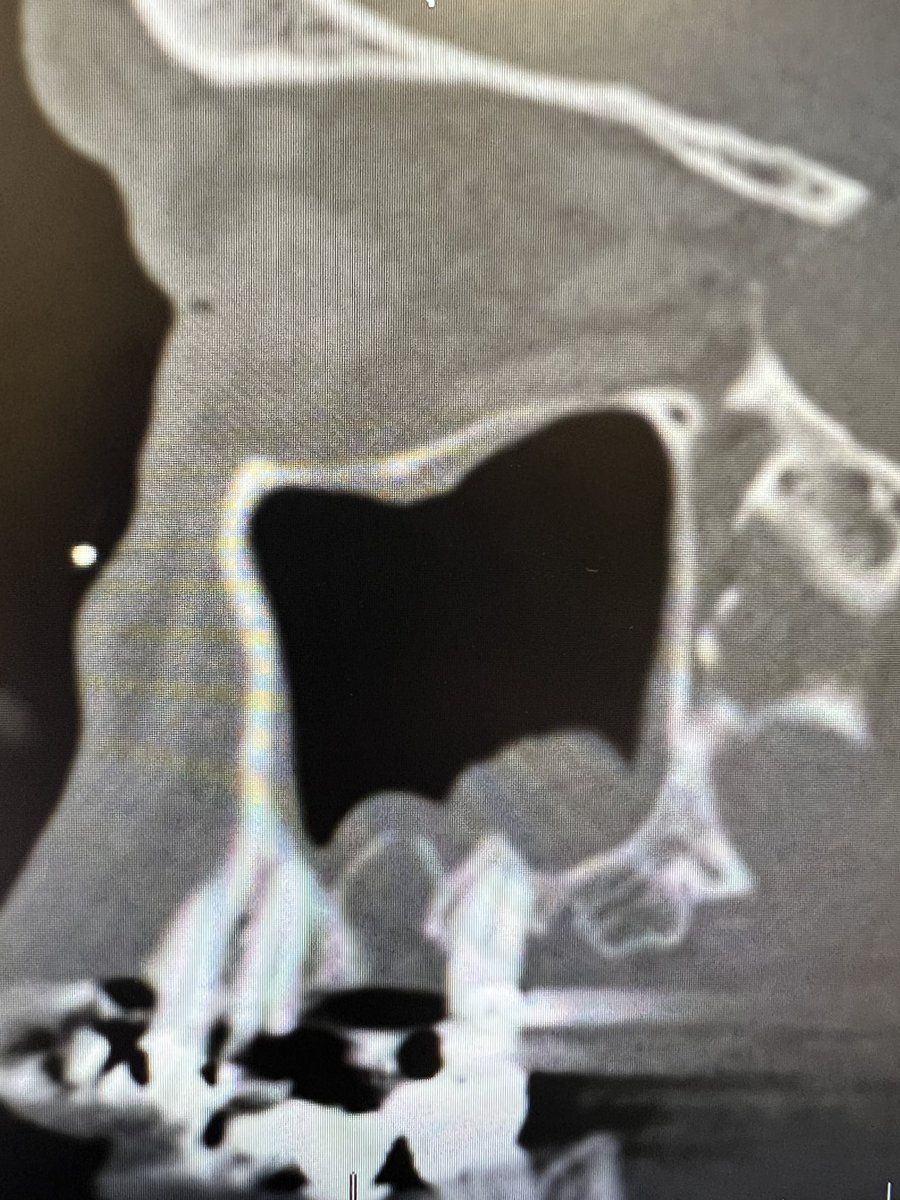

Kevin C. Welch, MD

@igotsinus

Professor Rhinologist, sinus surgeon and skull base surgeon. Wine Guy. WSET II, FWS, Rhône ML, Bordeaux ML #revisionsinussurgery #polyps #sinussurgery